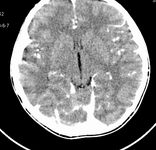

男,10岁,因近来常头痛就诊。先平扫拟诊右侧脉络膜裂囊肿,后薄层(3mm)扫描见此灶与右侧脑室后角相通,且向内几乎与鞍上池相连,并见一血管影沿其走形 (可能是脉络膜前动脉)。1。请教:脉络膜裂或脉络膜裂囊肿与侧脑室颞角或鞍上池相通吗?好像谁说脉络膜裂是脉络膜从外侧裂向侧脑室移行的裂隙。请高手讲讲这点的解剖关系。2。建议:对于老年患者,有丘脑附近特别是右丘脑附近的近似腔隙性梗死灶,临床症状不明显的,应做3mm薄层扫描,看病灶向下是否与侧脑室颞角相连,以免误诊。

薄层强化: